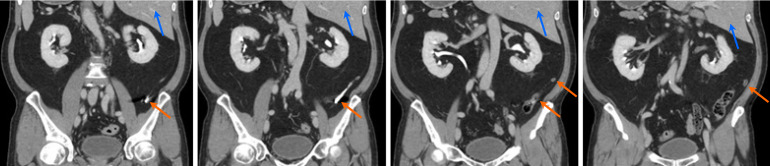

Results: Idiopathic pain was the most common diagnosis (104 cases, 45.2%), followed by appendicitis (46 cases, 20.0%) and diverticulitis (27 cases, 11.7%). Right lower quadrant pain predominantly revealed appendicitis (20.2%), whereas left lower quadrant pain frequently indicated diverticulitis (12.1%). Nonspecific pain cases have diverse etiologies. Rare conditions included situs inversus (one case) and intestinal malrotation (one case). Pregnancy-related diagnoses included acute appendicitis and uterine fibroid degeneration.